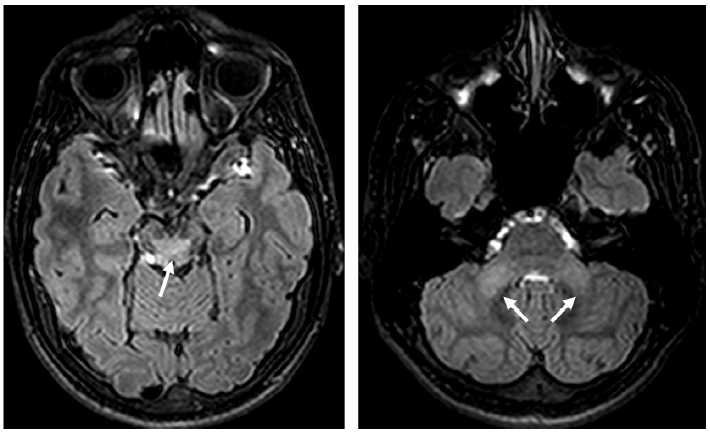

当存在糖尿病

或高血压

等心血管危险因素时,血管原因可能是急性小脑综合征的主要原因(图 1),并且血管病变可导致小脑实质部分萎缩(图 2)。

图 1 患有多种心血管危险因素的患者出现后颅窝多发性卒中。左:头颅MRI T2加权序列图像可见脑干和小脑实质存在高信号病灶(箭头)。中右:头颅MRI T1加权序列图像可见低信号病灶(箭头)。

图 2 血管性小脑病变。左:头颅MRI T2加权序列图像可见右侧小脑中脚急性血管病变。中:头颅MRI T2加权序列冠状位图像显示8年后同侧小脑半球萎缩。右:发病9年后随访的头颅MRI FLAIR序列图像显示小脑中胶异常信号和萎缩。